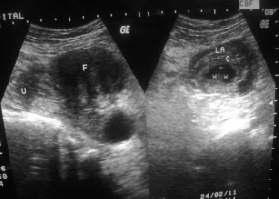

Ararecaseofrecurrent(consecutive)ectopicpregnancywithfibroiduterus

— Owvass Hamied Dar, Maqsood Ahmad Dar, Ghanshyam, Pankaj Sharma ....................................72